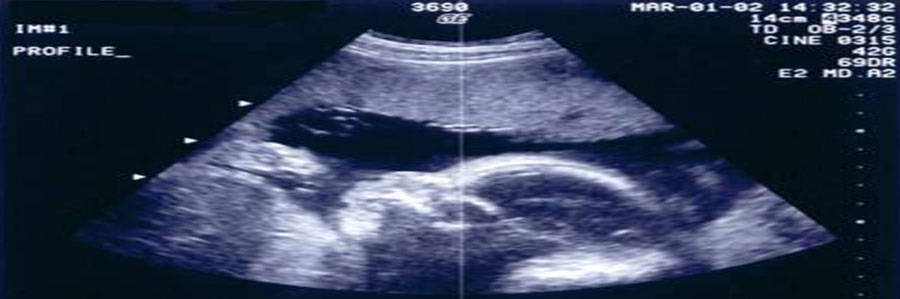

سونوگرافی یک تست تشخیصی است ، که در آن تصویربرداری با امواج فراصوت انجام می‌شود. بالا بودن فرکانس این امواج باعث می‌شود که توسط انسان قابل شنیدن نباشد.

هنگامی که امواج صوتی با مانعی برخورد می‌کنند، برمی‌گردند و از آنجا که بافت‌های مختلف داخل بدن، توانایی‌های متفاوتی در بازتاب امواج صوتی دارند، امواج بازتابش شده توسط کامپیوتر تحلیل شده و به تصویر تبدیل می‌شوند.

انجام سونوگرافی در طی دوران بارداری به عنوان روشی برای بررسی سلامت جنین (تعیین سن جنین، تشخیص ناهنجاری ها ومشکلات کروموزومی و...) مورد استفاده قرار می گیرد.